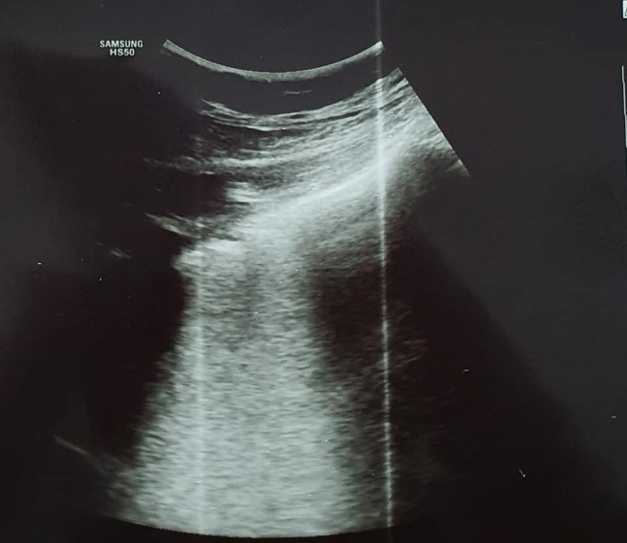

Pentru a demosntra existența formelor atipice ale bolii Covid-19, medicul din Craiova a făcut publice două imagini cu plănânii unei femei infectate cu noul coronavirus, care nu prezenta comorbidități.

„Forme atipice de Covid-19. Toţi medicii care se confruntă cu patologia Covid-19 ar trebui să se gândească la această boală şi în cazul unui pacient cu simptome ,,ciudate” apărute în plină stare de sănătate! Unii mă vor întreba ce înţeleg prin simptome ciudate! Medicii înteleg ce spun! Astăzi am depistat un caz de Covid 19 la o pacientă relativ tânără, fără febră, fără tuse..fără niciun simptom considerat tipic sau sugestiv pentru Covid-19! Faptul ca am folosit ecografia pulmonară ce mi-a relevat modificări sugestive, m-a convins de necesitatea unui examen CT pulmonar. Examinarea tomografică a fost concludentă. Ulterior, a urmat şi confirmarea serologică. Simptomele pacientei erau doar astenie marcată, ameţeli, somnolenţă. Saturaţia in oxigen 98%! Fără comorbidităţi!”, a scris medicul craiovean.

Publicând cele două imagini, medicul a arătat ce modificări au suferit plămânii pacientei confirmate cu SARS-CoV-2. Fiecare fotografie a fost însoţită de explicaţii.